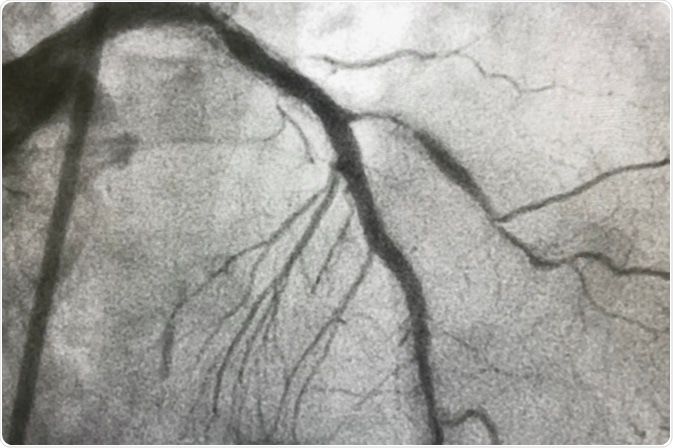

Image Credit: BelezaPoy / Shutterstock